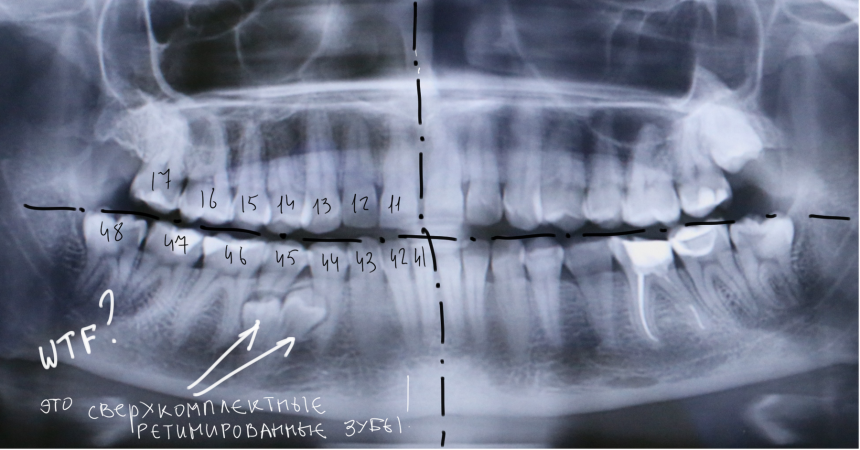

У моей пациентки мы случайно обнаружили два ретинированных сверхкомплектных премоляра:

При этом, весь комплект зубов на месте (за исключением правой верхней восьмерки — мы убрали её раньше).

Вот разбор снимка:

Давайте еще раз посмотрим на снимок:

Что мы на нем видим? Ну да,  есть два лишних зуба.

К сожалению,  мы не можем по ортопантомограмме…

• … достоверно определить положение зубов. Ортопантомограмма искажает.

• …определить их отношение к нижнечелюстному каналу и соседним зубам. Они находятся ближе к щеке или языку? Нижнечелюстной канал проходит за, между или перед ними? Мы должны ОБЯЗАТЕЛЬНО знать ответы на эти вопросы.

• … самое главное — спланировать операцию в целом и схему операционного доступа, в частности! Это важно? Еще как!

Кстати, по этим же причинам НЕЛЬЗЯ планировать операцию имплантации или остеопластики, основываясь на данных панорамного снимка. Всегда-всегда перед сложным лечением нужно делать компьютерную томографию.